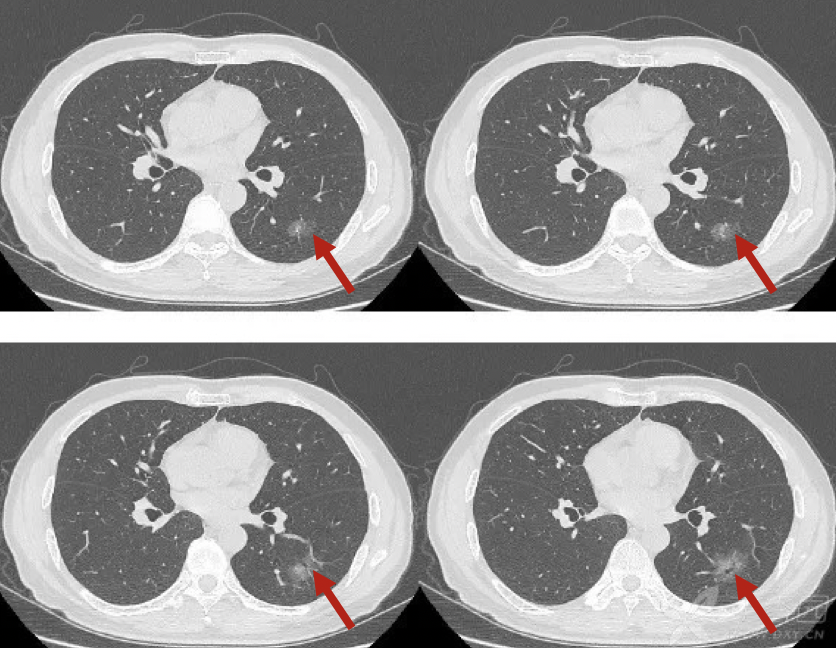

图4 肺腺癌患者的ct片可见 左下肺磨玻璃结节,边缘清楚,可见血管进入